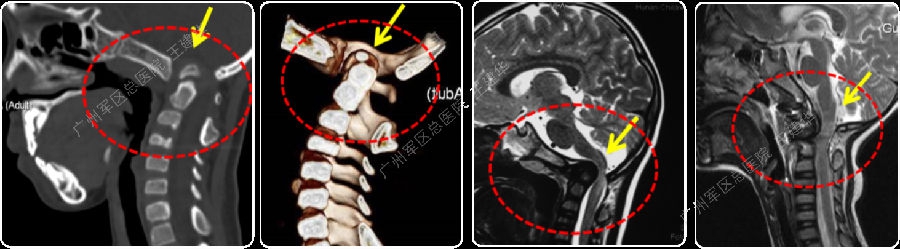

病例1

三维CT显示,患者曾行后颅窝减压手术

手术难点

(1)曾行后颅窝减压手术,骨质大量缺损,无法再行后路手术;

(2)寰齿之间及侧块关节之间有骨痂增生,阻挡复位。

术前术后对比